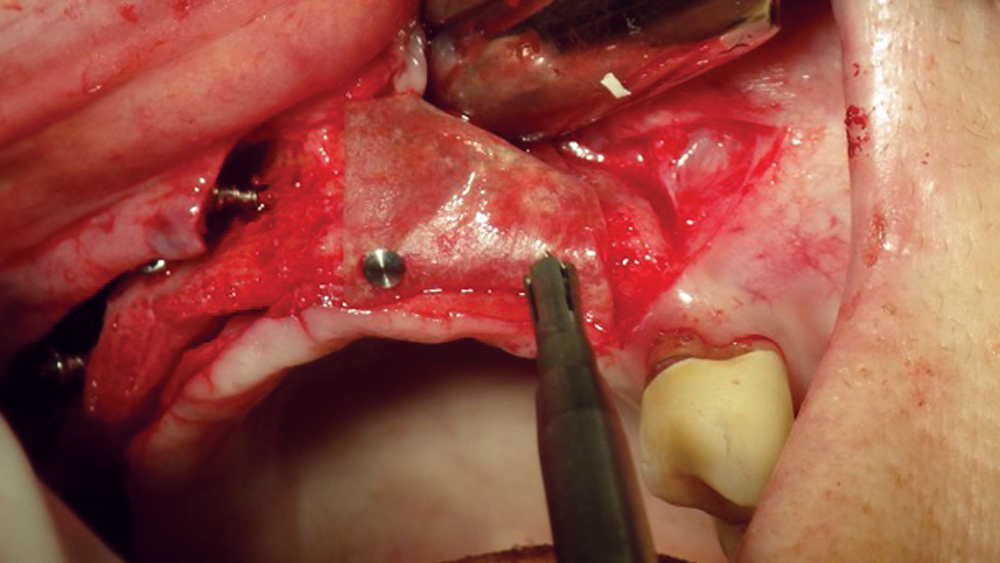

Titanium Mesh Membranes

Titanium mesh is a non-resorbable membrane that has been shown to be effective in maintaining space without collapsing. The membranes are flexible and can be bent and manipulated to form around the bony defect. The titanium mesh has demonstrated biocompatibility and features holes within the mesh, which allow for maintaining blood supply from the periosteum. The disadvantages of titanium mesh are increased wound dehiscence and difficulty in maintaining soft-tissue coverage (Figs. 4a, 4b). This may lead to increased infection and patient discomfort, which could lead to the necessity for early removal.

Figure 4a: Titanium mesh membranes have holes incorporated within the mesh

Figure 4b: Mesh exposure

Figures 4a, 4b: Titanium mesh membranes have holes incorporated within the mesh (4a), which allow for maintaining blood supply; however, these membranes have the disadvantage of increased wound dehiscence, which commonly involves exposure of the mesh (4b).